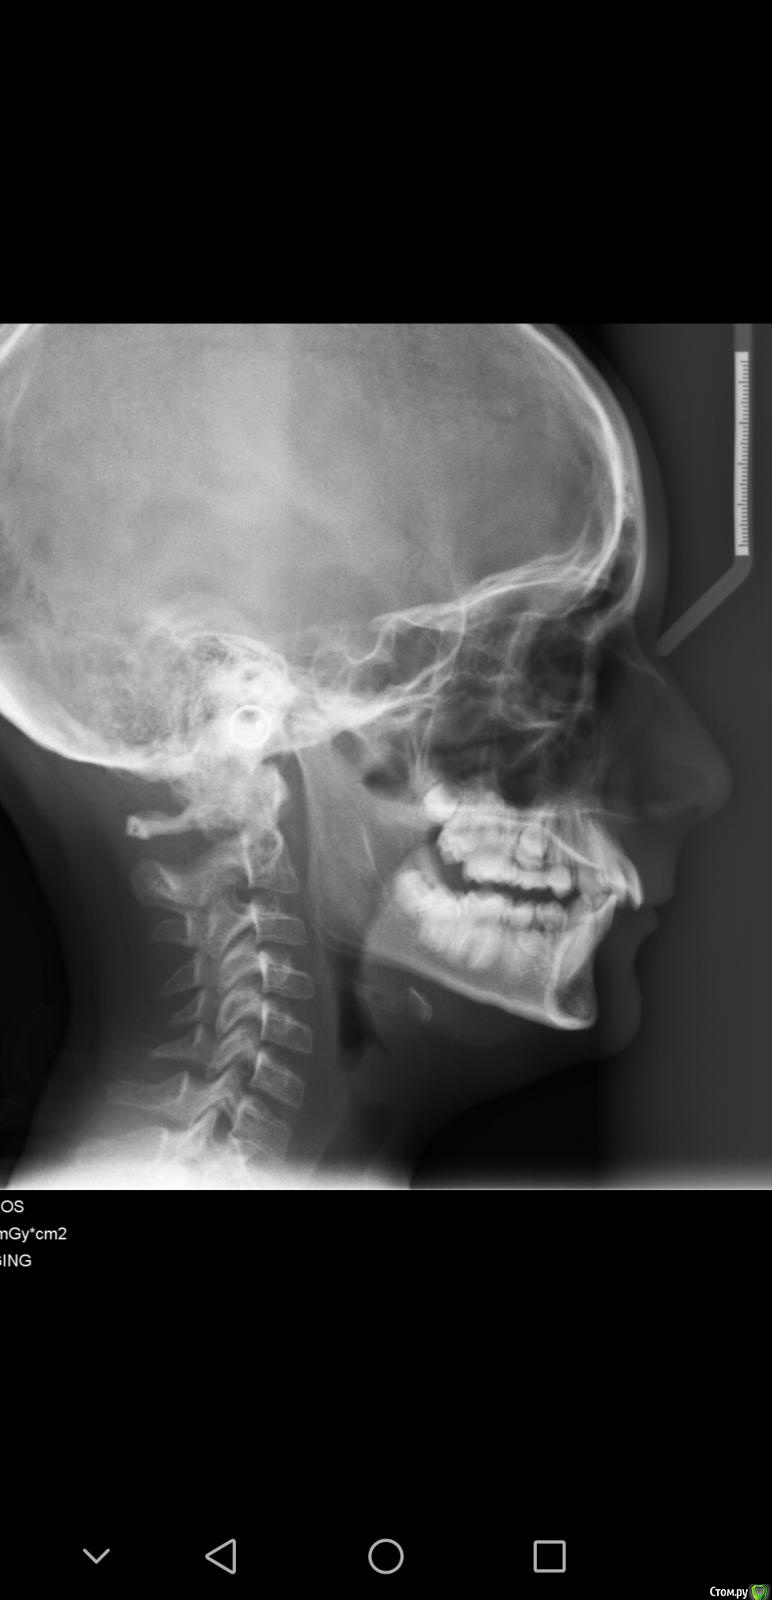

Chasiridou Опубликовано 19 февраля, 2020 Поделиться Опубликовано 19 февраля, 2020 посоветуйте терапию пожалуйста. мальчик 12 лет, верхняя челюсть выдвинута на 0.9 см вперед. снимки прилагаю. Ссылка на комментарий